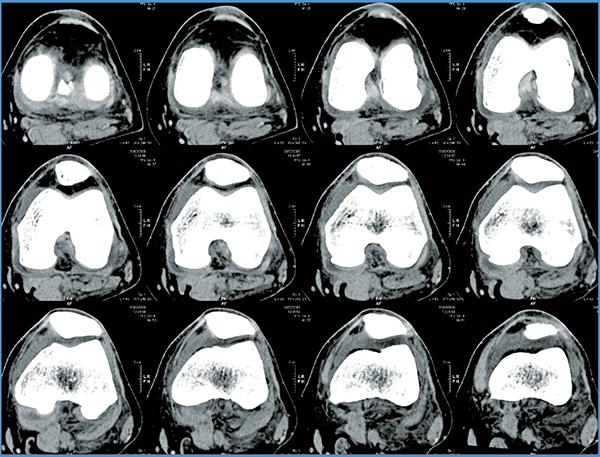

Mako Robotic-Arm Assisted Technology provides you with a personalized surgical plan based on your unique anatomy. First, a CT scan of the diseased hip or knee joint is taken. This CT scan is uploaded into the Mako System software, where a 3D model of your hip or knee is created. This 3D model is used to pre-plan and assist your surgeon in performing your joint replacement procedure.

Step 1. Knee CT Scan

Step 2. Knee Personalized Planning